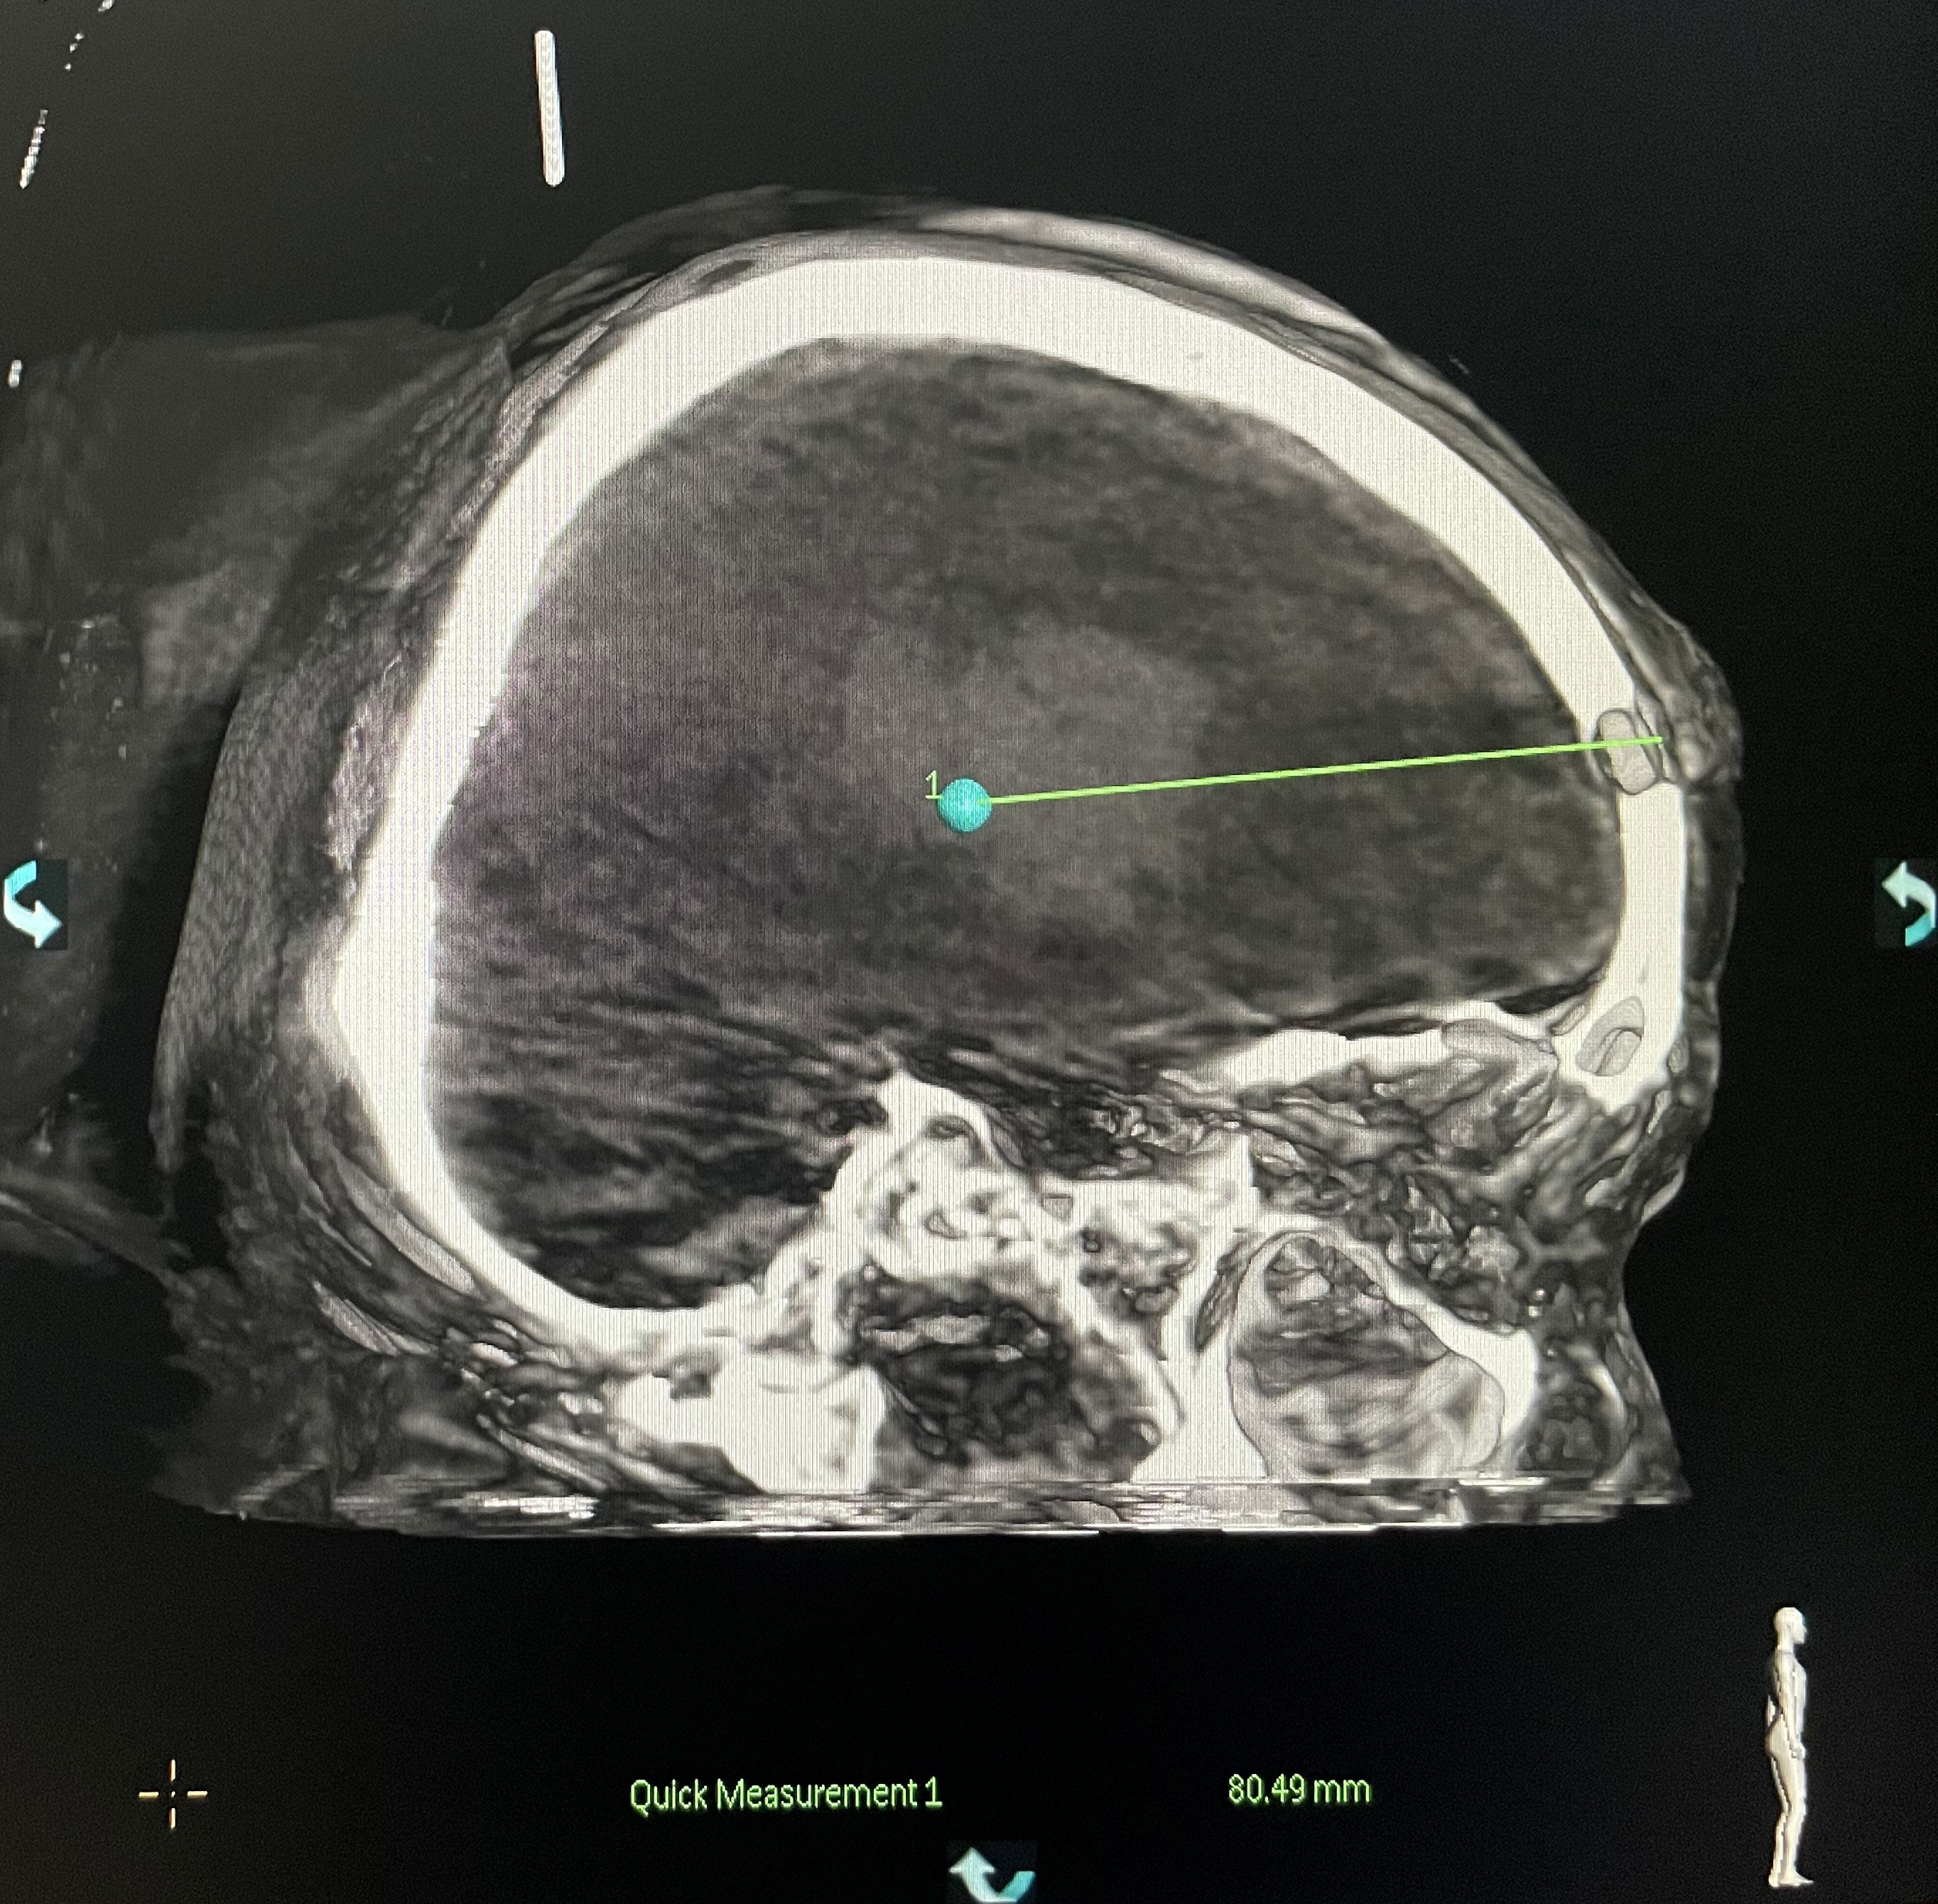

The surgical incision site was marked with a metal object on the forehead, approximately 2 cm from the midline and 3 cm from the orbit on the hematoma side (Figure 2). The priority was to make an incision in the frontal stria and avoid the frontal sinus to prevent cerebrospinal fluid leakage after surgery and ensure an aesthetically pleasing appearance after wound healing. A hole was drilled in the bone at the metal mark (Figure 3). The C-arm CT function of the digital subtraction angiography (DSA) machine was used to collect the original data for processing; display the coronal, sagittal, and axial CT images; mark the center of the hematoma; and set it as the target site for the puncture (Figure 4). The 3D reconstruction of brain tissue was performed using the 3D reconstruction software Xper CT of the DSA machine, and the bone hole displayed in gray scale was adjusted as the puncture point. Subsequently, the 3D stereo image was rotated, overlapping the puncture point and puncture target. The laser emission direction was determined using the principle of “two points and one line,” and the real-time 3D reference image working angle was recorded (Figure 5). The skull was cut along the coinciding point, and the distance between the puncture point and the puncture target was measured as the puncture depth (Figure 6).

The DSA machine was used for CT scanning, collecting data, and transmitting the information to a computer. It was ensured that the drainage tube was located at the center of the hematoma (Figure 9).